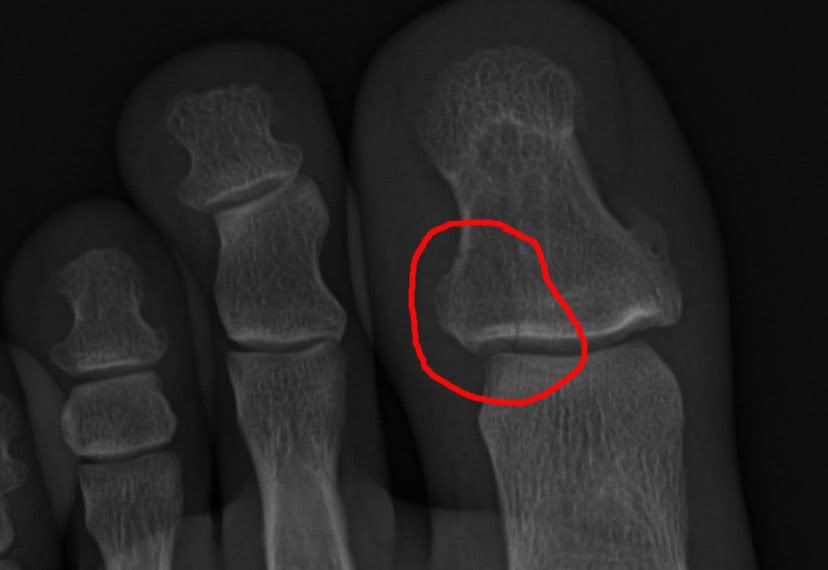

Well I joined the injury club last night. Was wrapping up a piece of cocktail glass for shipment when I dropped the roll of shrinkwrap. Well in my infinite wisdom I did not want it to slam into my kitchen floor, so I went to grab the falling roll. As I went to grab it the roll slammed into my foot and a millisecond later my hand smashed into the top of the roll. After wailing in pain and almost passing out I finally took my sock off to see what I had done. Ripped the top skin right off the big toe and blood, but not bleeding too bad. So I was starting to think it was just a skin abrasion. After about a half hour I told the wife to drive me to the immediate care center. Was a good choice because after 2hrs there I limped out with a broken toe and a broken finger, both on my left side.

I tried to get the xray pics posted but the software they game me with them only allows me to view it. I am off work today so I will play around with it some more.